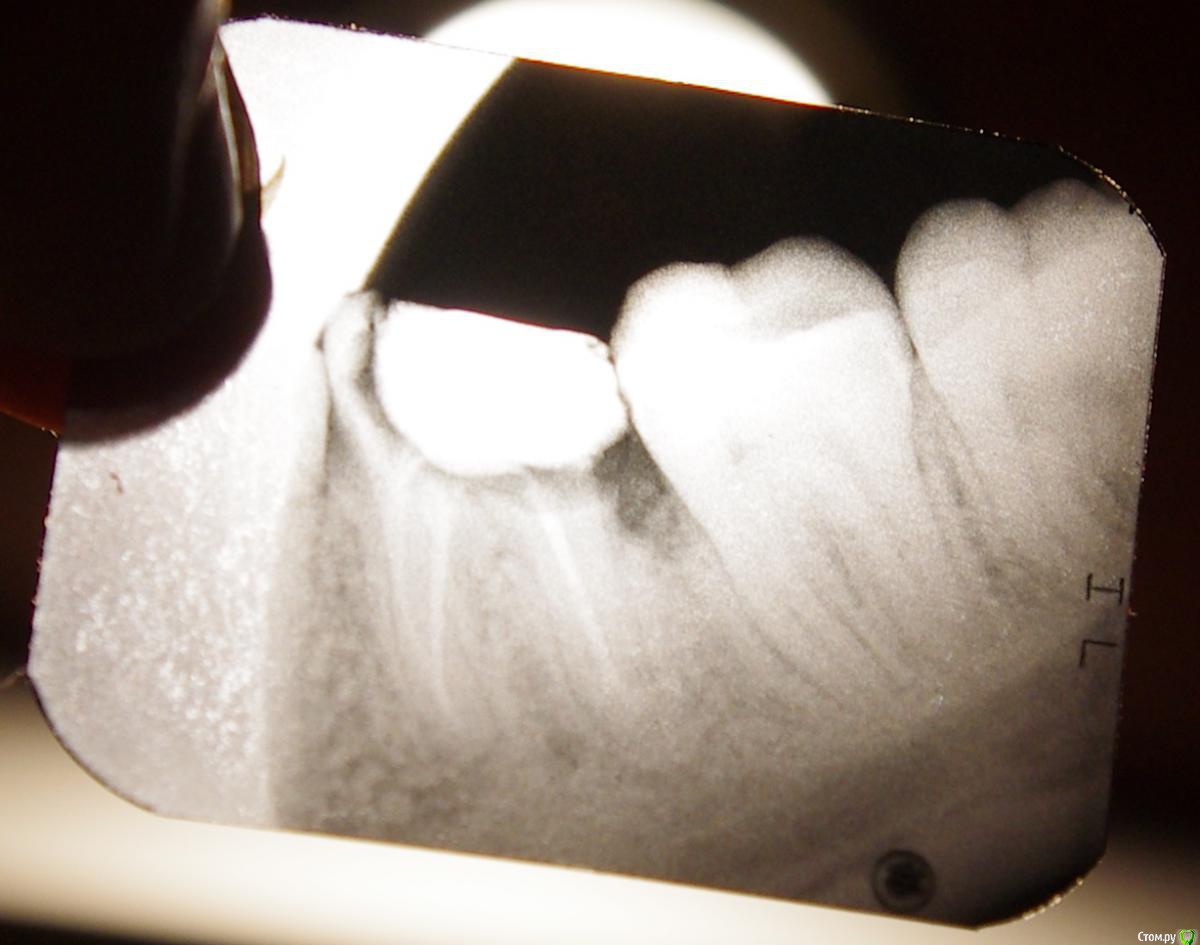

Miss_teacher Опубликовано 10 декабря, 2014 Поделиться Опубликовано 10 декабря, 2014 Добрый день! Хотелось бы узнать мнение специалистов о возможности сохранения зуба (снимок прилагается).Ситуация следующая: зуб нижний с левой стороны, 6й от центра, корни запломбированы, несколько раз ставили пломбу, но были оставленны слишком тонкие стенки, поэтому зуб крошился и пломбы постоянно выпадали. В последний раз стоматолог сказал, что постоянную пломбу прикреплять уже не к чему, нужно удалять зуб и поставил временную.Хотелось бы узнать мнение специалистов - возможно ли сохранить зуб?Много читала про восстановление коронковой части зуба с помощью внутрекорневых вкладок и стекловолоконных штифтов, насколько это применимо в данном случае? Ссылка на комментарий

SashaDoc Опубликовано 11 декабря, 2014 Поделиться Опубликовано 11 декабря, 2014 По снимку определяется глубокий кариес корня - показание для удаления зуба. Ссылка на комментарий